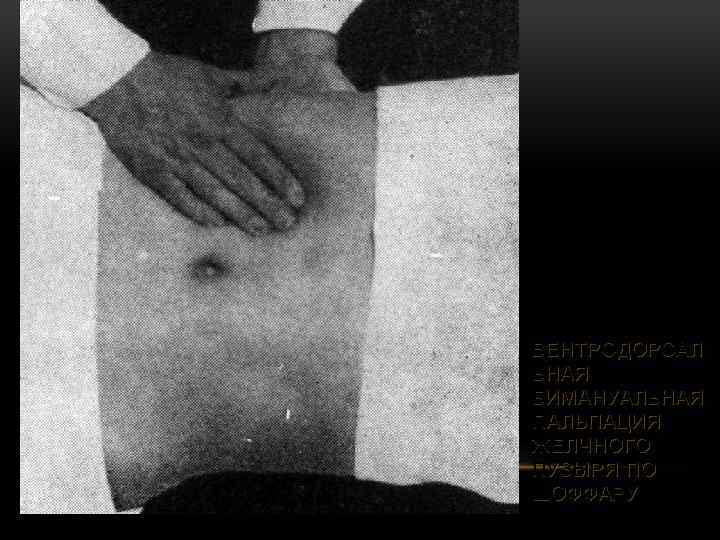

ВЕНТРОДОРСАЛ ЬНАЯ БИМАНУАЛЬНАЯ ПАЛЬПАЦИЯ ЖЕЛЧНОГО ПУЗЫРЯ ПО ШОФФАРУ

ВЕНТРОДОРСАЛ ЬНАЯ БИМАНУАЛЬНАЯ ПАЛЬПАЦИЯ ЖЕЛЧНОГО ПУЗЫРЯ ПО ШОФФАРУ